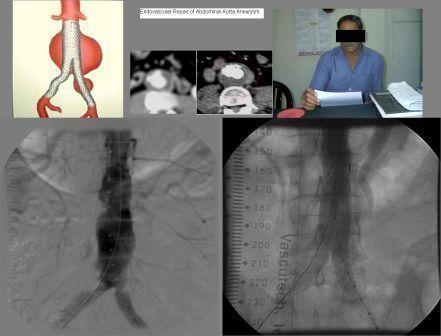

stent graft in subclavian artery aneurysm